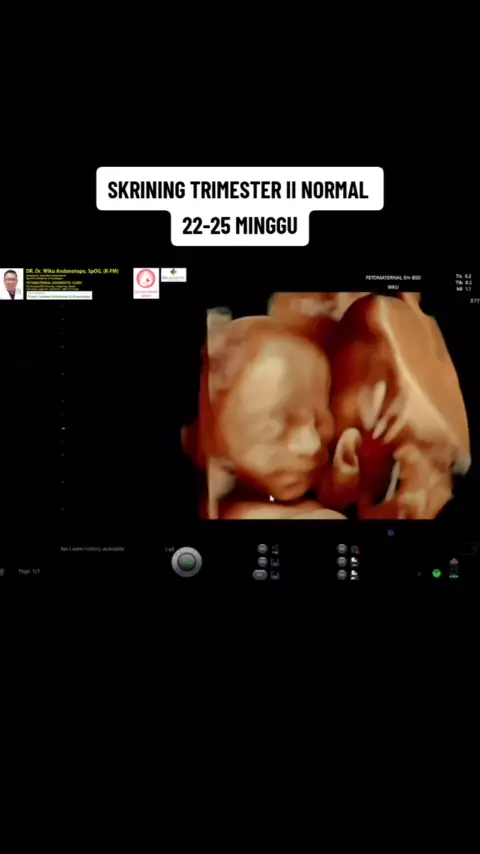

Skrining trimester II normal, antara 22-25 minggu#skriningkehamilan#trimesterkehamilan#trimester2#pregnancyjourney#pregnant#skriningfetomaternal#edukasikehamilan#usgkehamilan#usgkehamilansehat#trimester3#fetomaternalserpong#usgfetomaternal#edukasi#fetomaternalbsd#fetomaternalserpong#usgfetomaternaltangerang